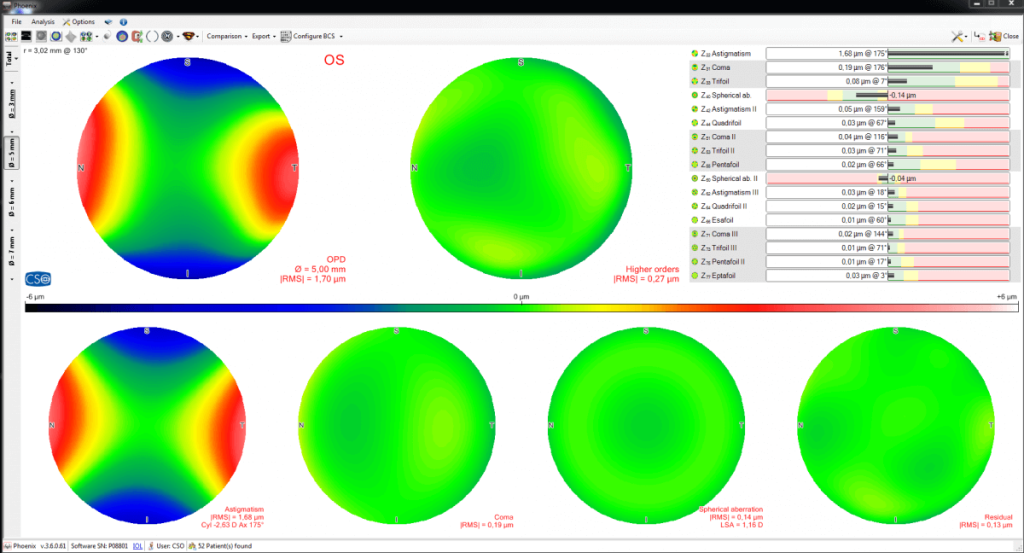

CORNEAL ABERROMETRY

Aberrometric analysis offers a complete overview of the corneal aberrations. It is possible to select the contribution of the anterior, posterior or total cornea for different pupil diameters. The OPD/WFE maps and the visual simulations (PSF, MTF, image convolution) can help the clinicain in understanding or explaining the patient’s visual problems.